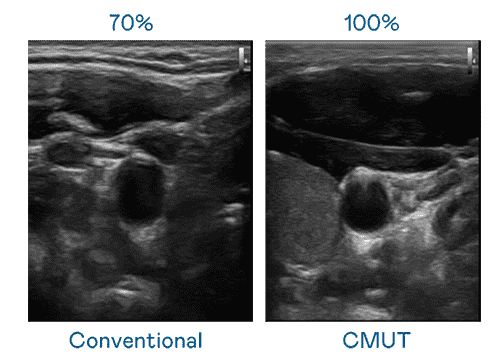

CMUT 技术是一种用电容式微机电元件来产生超音波讯号的技术。。。与传统 PZT 压电式技术相比,,,CMUT 频宽增加 30%,,,更宽频的超音波讯号让影像解析度大幅提升,,,,是实现高影像品质医疗超音波扫描、、、促进精准医疗发展的关键技术。。。。

大频宽带来超清晰影像

超音波影像的解析度高低,,,首先取决于探头能发出的讯号频宽。。。z6尊龙 CMUT 可提供高清晰的超音波讯号,,,提供高频宽、、、、高灵敏度、、、、影像纹理细节更高的超音波影像,,,,协助医护人员缩短影像判读时间及利用精准的医疗影像进行诊断。。。。